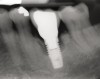

Fig 17. Radiograph showed symmetrical infrabony defect affecting 50% of the implant surface.

Figure 17

Clinical examination showed 2 mm of buccal recession with a shallow vestibule and absence of keratinized attached gingiva against the crown with 8 mm of circumferential pocketing accompanied by bleeding upon probing (Figure 15 and Figure 16). A periapical radiograph showed a symmetrical vertical osseous defect causing the loss of 50% of the bone around the implant (Figure 17). Because the patient had made a significant investment of time and finances to replace her lost tooth with the implant, she desired that the implant and restoration be retained, if feasible.